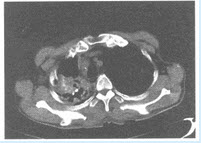

男,67岁,吸烟史45年,既往有肺结核病史。近1个月低热、咳嗽、咳痰,咯血两次,常规抗感染治疗后复查胸部CT,右上肺病灶如图。

(多选题)可能的诊断有哪些()

A:肺结核

B:念珠菌感染

C:大叶性肺炎实变期

D:周围性肺癌

E:耐药菌性肺炎